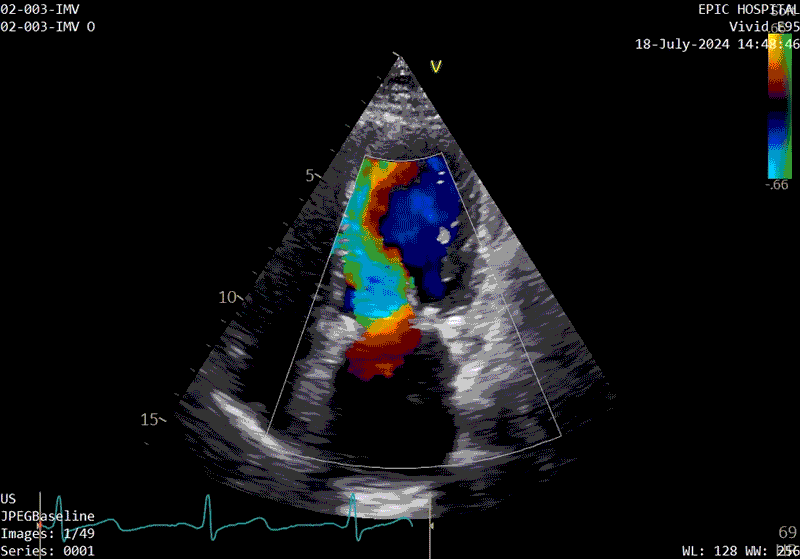

The patient’s echo at one-year after polymer valve implantation

The patient’s echo at one-year after polymer valve implantation. After replacement with a polymer valve, rapid ejection and laminar flow pattern into the left ventricle can be seen, and the opening and closing of the leaflets in the cardiac cycle are relatively quick compared with traditional valves.